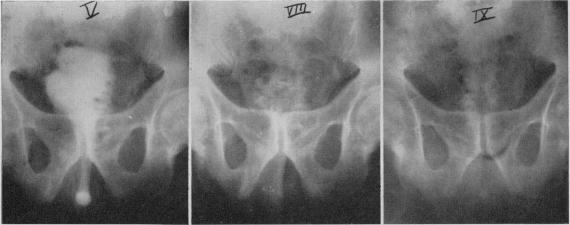

Sigmoid segment substitutes for bladder.